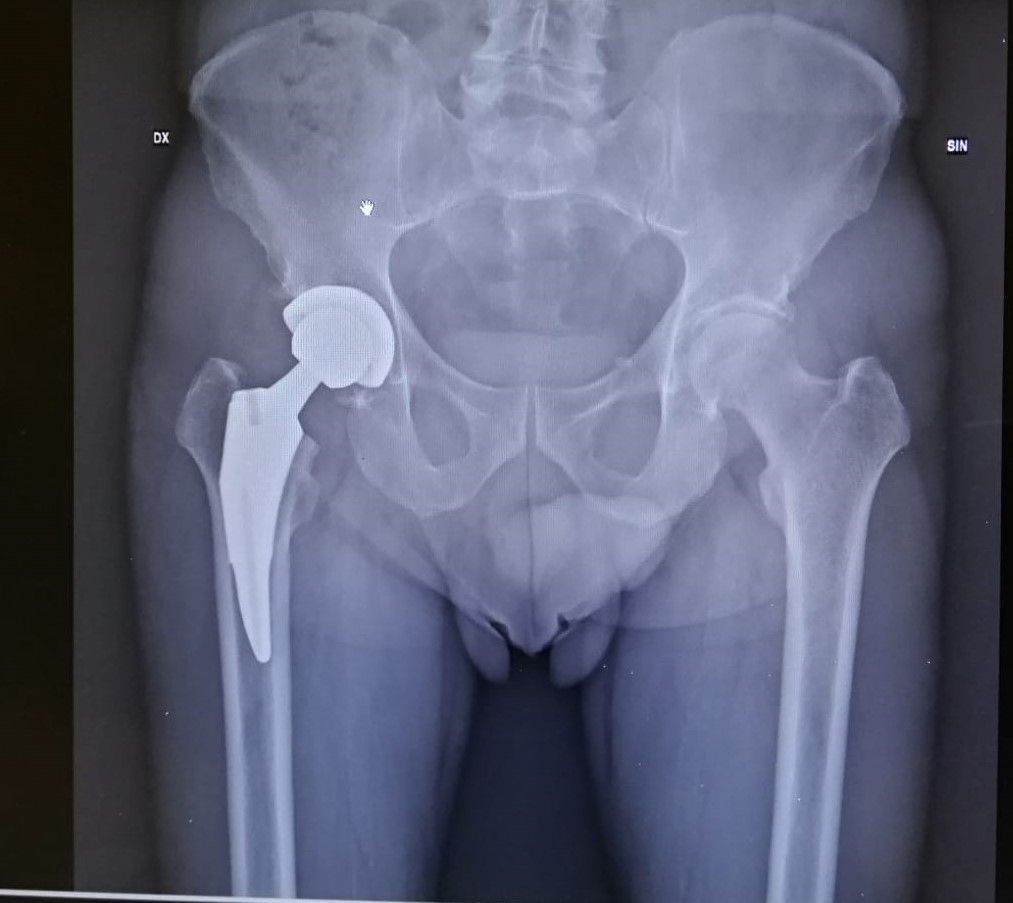

- Protesi totale d'anca mini-invasiva (DAA)

Sono stato operato dal Dott. Zornetta per una protesi all' anca, medico molto competente, disponibile attento alle problematiche del paziente.Mi sono trovato molto bene.

Preciso e chiaro nelle spiegazioni. Sempre presente anche dopo l' intervento(anca). Una garanzia per gli sportivi.